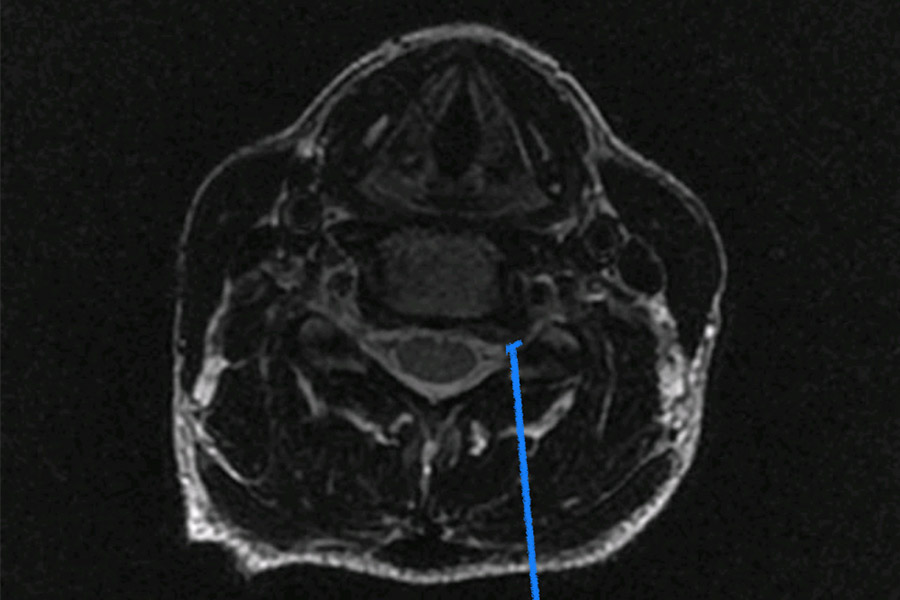

Caso clínico: endoscopia de columna multinivel L4L5 y L5S1

Los síntomas que presentaba el paciente eran dolores acentuados en las piernas, claudicación a la marcha y calambres y hormigueos en las piernas.

Durante la intervención quirúrgica, se abordarán los dos niveles mediante la técnica de endoscopia de columna.